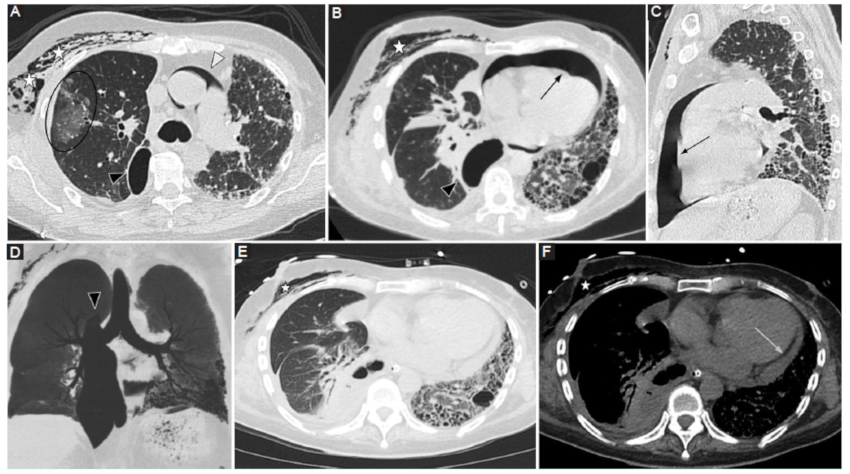

Pericarditis aguda

Se define como un síndrome pericárdico de tipo inflamatorio que puede darse con o sin DP acompañante («pericarditis seca»)6.

En la mayor parte de los casos se trata en un cuadro idiopático (presumiblemente asociado a infecciones virales), aunque puede manifestarse en el contexto de enfermedades sistémicas como tuberculosis, enfermedades autoinmunes, como hallazgo o complicación posquirúrgica, o asociado a compromiso miocárdico (Figs. 5, 6 y 7) (5,6.

Si bien tradicionalmente se la describe en su forma aguda, también puede darse en curso subagudo o crónico. Los síntomas clásicos de presentación incluyen: dolor torácico agudo, de tipo pleurítico que cambia de intensidad con la posición y signos de fricción pericárdica. Los cambios clásicos en el electrocardiograma (ECG) y la elevación de marcadores serológicos de inflamación apoyan el diagnóstico6.

Entre los signos clásicos de pericarditis aguda por TCMC se describen:

DP: particularmente del tipo exudado, aunque en una minoría de casos puede ser trasudado10.

Engrosamiento del pericardio. Habitualmente las hojas del pericardio miden entre 1,3 y 2,5 mm. Un aumento mayor a 4 mm presenta una alta especificidad para esta patología10.

Realce pericárdico tras la inyección de contraste endovenoso (alta especificidad) (10.

Cabe mencionar que Hammer et al. (10, en su serie de 46 pacientes con diagnóstico de pericarditis aguda, encontraron que el engrosamiento y realce pericárdico valorado por TCMC presenta una sensibilidad del 54-59% y una especificidad del 91-96%10.

Compromiso del pericardio por patología tumoral

Los tumores del pericardio se clasifican en benignos (lipomas y fibromas) o malignos (mesotelioma, linfoma y sarcoma). Si bien son raros, dentro de ellos el más frecuente es el mesotelioma, con un pronóstico ominoso. Por su parte, las metástasis representan la neoplasia más frecuente del pericardio, siendo los tumores primarios involucrados: pulmón, mama, linfoma y melanoma (Fig. 8) (6.

Los métodos por imágenes revelan la presencia de compromiso pericárdico, así como signos de afectación extrapericárdica (parénquima pulmonar, estructuras mediastinales y óseas). Los hallazgos por TCMC presentan una amplia variabilidad de presentación, entre los que se menciona:

DP, generalmente del tipo exudado.

Engrosamiento irregular del pericardio.

Lesiones nodulares y masas pericárdicas.

Adenomegalias mediastinales (definiéndose como ganglios linfáticos mayores a 10 mm en su eje corto).

En este sentido, resulta mandatoria la correcta diferenciación entre recesos pericárdicos voluminosos y ganglios linfáticos patológicos mediante métodos por imágenes1,6,11.

Puede presentarse DP en cuantía variable como signo de infiltración tumoral directa, aunque hasta en dos tercios de los pacientes se debe a causa no tumoral6,12. Al respecto, Thurber et al. (13, en su estudio de más de 13,000 autopsias, encontraron 189 casos de afectación tumoral del pericardio, siendo el DP el hallazgo más frecuente. Aún más, concluyeron que hasta un 85% presentaba DP de tipo fibroso, lo cual traduce la presencia de un exudado13.

Por último, los métodos por imágenes permiten discriminar entre la presencia de pseudomasas (como una almohadilla epicárdica prominente) de tumoraciones pericárdicas2.